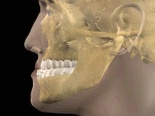

Malocklusioner

Överbett Underbett

Malockusion innebär en avvikelse i relationen mellan käkar och tänder. Exempel på detta är underbett och överbett.